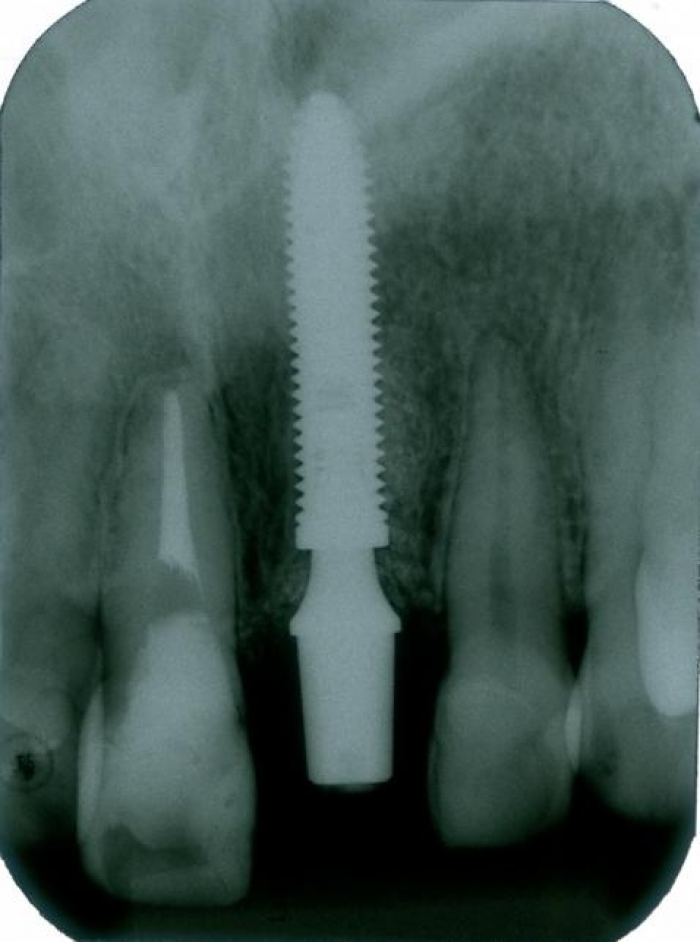

Raio X inicial

Raio X com implante e prótese provisória fixa